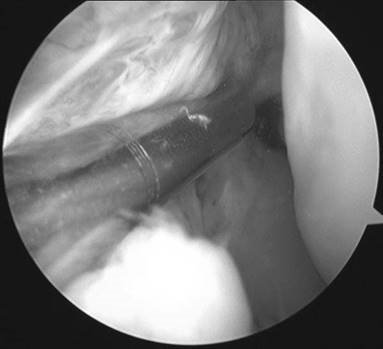

A 25-year-old football player sustained a twisting injury to his left knee. He has already had an arthroscopy at โ€˜St Elsewhereโ€™ and brings intra-operative pictures to show you.

Illustration 10 for Ace FRCS Orthopaedics: Oxford University Press Adult Pathology Viva

๐Ÿ” Click to enlarge

Clinical Radiograph / Orthopedic Image

What does his arthroscopy picture show?

The limited view shows a bare lateral wall of the femoral notch, in keeping with a complete ACL rupture.

What is important in your initial assessment of this patient?

The history of the injury, specifically how long ago

Symptoms since the injury: continued instability, locking, and significant subsequent injuries (is this an acute medial meniscus tear?)

Occupation and sporting aspirations

Expectations

Co-morbidities: diabetes mellitus, collagen disorder

Previous surgery

O n examination: fi xed fl exion deformity; comfortable ROM; sign of meniscal pathology; signs of ACL disruption โ€” Lachman and pivot tests (both can be negative in cases with bucket handle meniscal tears as the displaced meniscal tissue provides some increased stability to the knee); evidence of other ligament injury. If the patient has had signifi cant secondary injuries it can be useful to get a fresh MRI scan to assess for secondary meniscal injuries.

The patient now has recurrent instability and has been unable to return to sport. Your examination confi rms an ACL injury and he has a full ROM. What are the management options now?

T here are two factors to address here: (1) treatment of the ACL and (2) treatment of any associated meniscal injury.

ACL injuries can be managed non-operatively and operatively. An assessment needs to be made of the risks of further meniscal injuries as this predicts the likelihood of early osteoarthritis.

Risk factors for high meniscal injury include: young age; level 1 sports; high number of hours participating in sport per week and previous meniscal injury. In view of this patientโ€™s history I would recommend an ACL reconstruction. The medial meniscal injury requires surgery. The key decision is whether to repair or resect the unstable meniscal tissue. Factors that would make you wish to repair the meniscus would be: recent injury (and easily reducible); redโ€“red or redโ€“white injury; concurrent ACL injury (increased healing rates); young age (it is also worth noting that the results of lateral meniscal repairs are better than those for medial meniscal repairs).

My choice would be to perform an arthroscopic ACL reconstruction and concurrent meniscal repair if indicated.

You have decided to reconstruct the ACL. What graft would you use?

[Have a view yourself.] I would use a four-strand hamstring graft with suspensory femoral fi xation (EndoButton) and RCI screw fi xation on the tibial side. But one should also be aware of the other options, as there advantages and disadvantages.

Autograft

z Hamstring tendons: good long-term results and low donor site morbidity but slower healing into bony tunnels

z Patella tendon: good long-term results, but donor site morbidity

Allograft

z Typically the Achilles tendon: no donor site morbidity but infection risk and, depending on sterilization techniques, less strong โ€” and also expensive z Artificial โ€” avoid